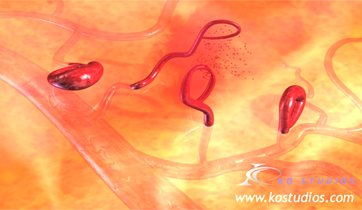

Diabetic Retinopathy

ScienceProd, Paris

Diabetic retinopathy is a condition resulting from micro-vascular retinal changes. Lack of oxygen in the retina stimulates release of VEGF, a factor that causes new blood vessels to grow along the retina and in the vitreous humour. These new blood vessels can destroy the retina by bleeding.